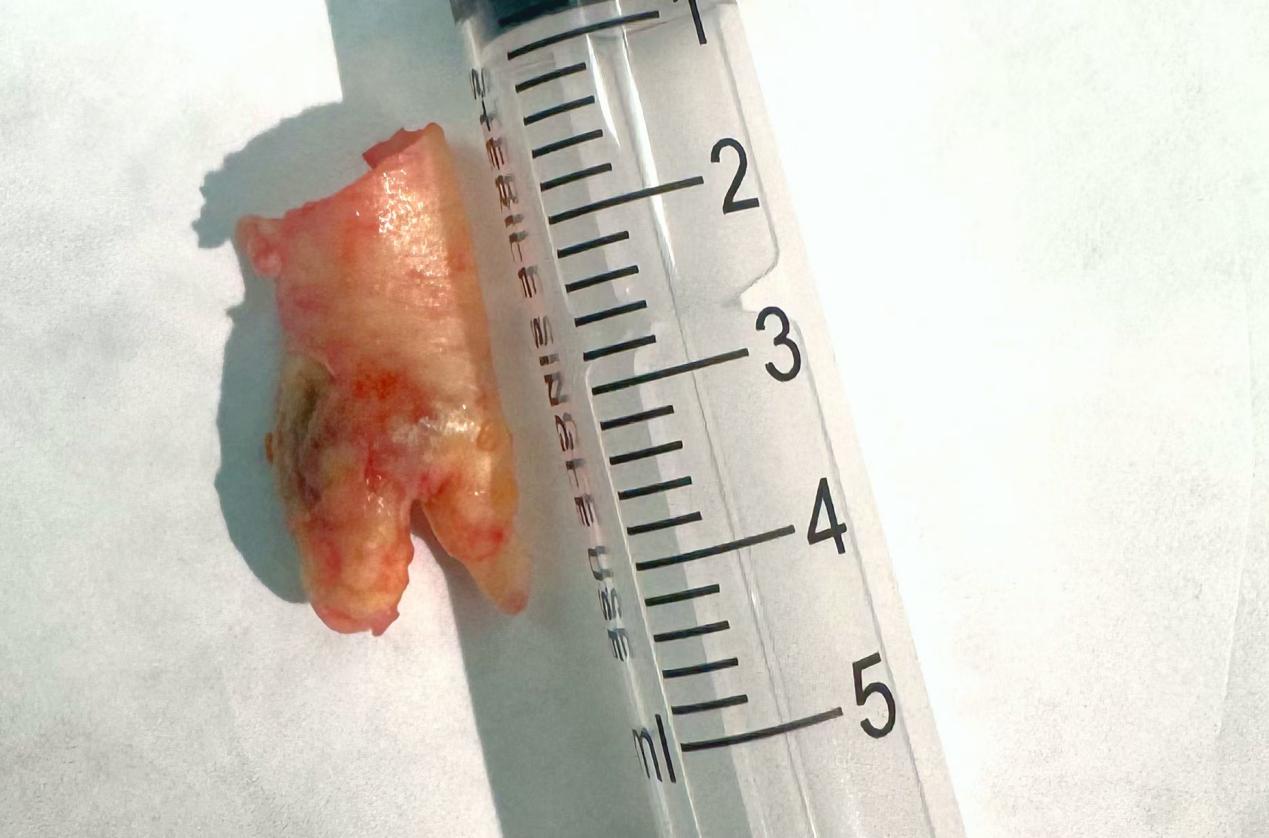

4月底,神经外七科团队为刘强进行了颈动脉内膜剥脱术。“术中剥出一段手指头粗、形似‘猪蹄’样质地坚韧的斑块,并修复破坏的血管内膜,彻底‘疏通’血管。”参与手术的神经外七科罗似亮主治医师说。

图:从颈内动脉剥下的斑块,如手指头粗